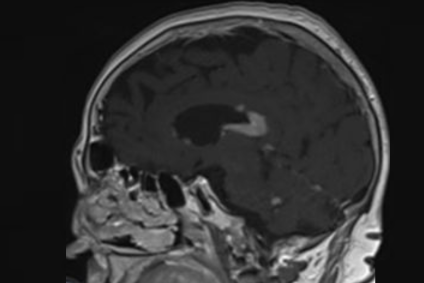

Linfoma cerebral

Neurocirugía Barcelona (s.f.). Son tumoraciones que epidemiológicamente representa menos del 3% de todas las tumoraciones cerebrales. [Fotografía]. Recuperado de www.neurocirugiabarcelona.com

La fisiopatología de esta condición se encuentra relacionada con alteraciones en las células B, incluyendo mutaciones en los genes MYD88 y CD79B, que fomentan el crecimiento celular descontrolado. Así, el presente tipo de linfoma representa aproximadamente el 4 % de los tumores cerebrales malignos y el 6 % de los linfomas extranodales. Asimismo, aunque es altamente quimiosensible, las tasas de recaída siguen siendo elevadas, lo que subraya lo fundamental de un diagnóstico temprano y un manejo eficaz (Schaff y Grommes, 2022).

Con una presentación clínica variable, incluye déficits neurológicos focales, alteraciones cognitivas, cambios en el comportamiento y, en algunos casos, síntomas de hipertensión intracraneal como náuseas y vómitos. En consiguiente, su diagnóstico requiere un alto grado de sospecha clínica y el uso de herramientas avanzadas como la resonancia magnética (functional magnetic resonance imaging, fMRI, en inglés). Siguiendo esta línea, las principales características del linfoma cerebral son las siguientes:

• Localización de las lesiones: Frecuentemente, afecta estructuras profundas como el cuerpo calloso y los ganglios basales.

• Patrón de crecimiento: Infiltración angiocéntrica que se extiende a lo largo de los vasos sanguíneos.

• Diagnóstico por imagen: Lesiones homogéneamente realzadas con contraste y edema leve.

• Sintomatología progresiva: Los síntomas suelen desarrollarse durante semanas o meses.

• Alta quimiosensibilidad: Responde bien a regímenes de quimioterapia de dosis alta con metotrexato.